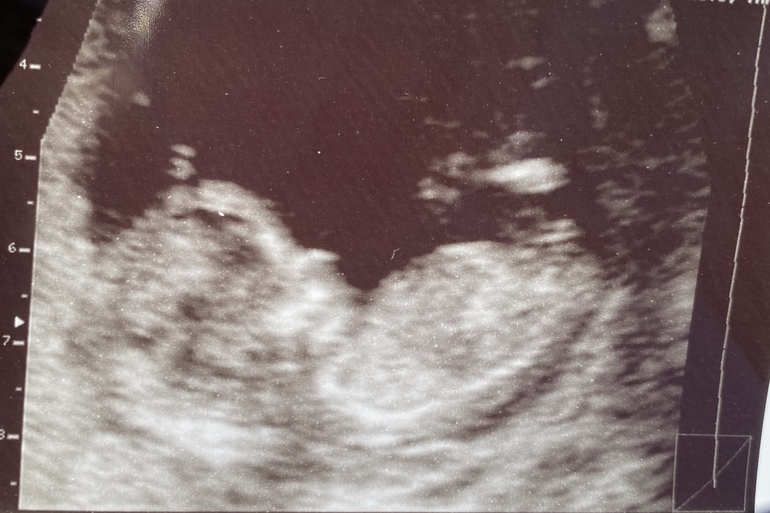

Первый скрининг 😍😍😍

ТТТ оказалось все хорошо. УЗИ выполняла в ЖК. Врач попалась чудесная, все рассказала и показала.

Срок по месячным 12+6, по узи 12+3, но так всегда было , цикл 30 дней.

КТР 61. ТВП 1.6. Нос определяется)) ЧСС 150

Врач показала мне , как малыш трёт ручками лицо. Это так трогательно и интересно 🥰

Все органы на месте, шейка моя тоже хорошая, в общем пока я спокойна 😄

Ещё предположили пацана. На 16 неделе сходим уже вместе с мужем посмотрим на пол малыша ☺️